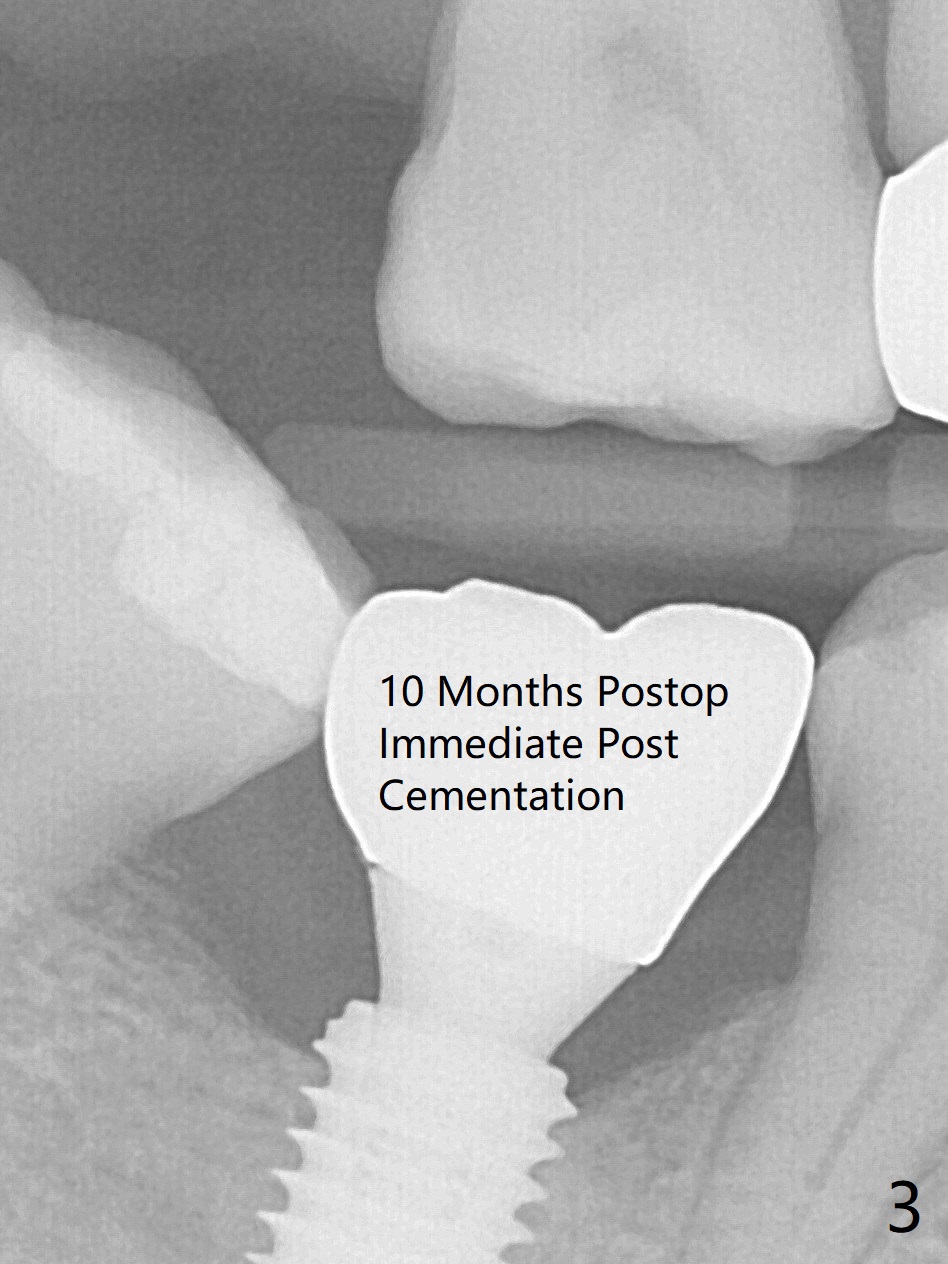

In fact 5x10 mm implant placement with guide requires using 5 mm cortical tap (Fig.1). When a 6x4 mm healing abutment is placed slightly supragingival, the clearance with the opposing supraerupted tooth is ~ 2 mm. It suggests that orthodontic intrusion is required for restoration. In fact the patient is incompliant with orthodontic mini-implant placement and retraction. When the implant at #31 is osteointegrated 4.5 months postop (Fig.2), it is used an anchor with an abutment and a provisional to intrude the opposing tooth. The final crown is cemented 10 months postop (Fig.3) with occlusal clearance (Fig.3' *). The contacts between #2 and 3 and between #31 and 32 are loose with papillary inflammation 5 months post cementation. It is planned to remove #31 crown/abutment for pick up impression/porcelain addition. Instead the crown is removed. After removing #32 MO composite with minor 2nd caries, new composite is placed (Fig.4 *) while the crown is reseated. When the crown is recemented, bitewing shows open margin (Fig.4), but the contact is wide and tight. After occlusal adjustment, occlusal contact at #31 and 32 mesial is heavier than that at #30. #3 crown is recommended. The occlusal table difference betweeen the upper 1st and 2nd molar is ~ 2 mmm preop (Fig.4'), whereas the difference is ~ .6 mm postop (in combination of occlusal equilibrium and intrusion of the upper 2nd molar (Fig.4)). It seems that orthodontic intrusion is not efficient in a male with bruxism. There is mild lingual (L) and distal bone loss 1.5 years post cementation (Fig.5) when CT is taken for #3 immediate implant. Lower Molar Immediate Implant, Armaments Xin Wei, DDS, PhD, MS 1st edition 07/12/2018, last revision 11/28/2020